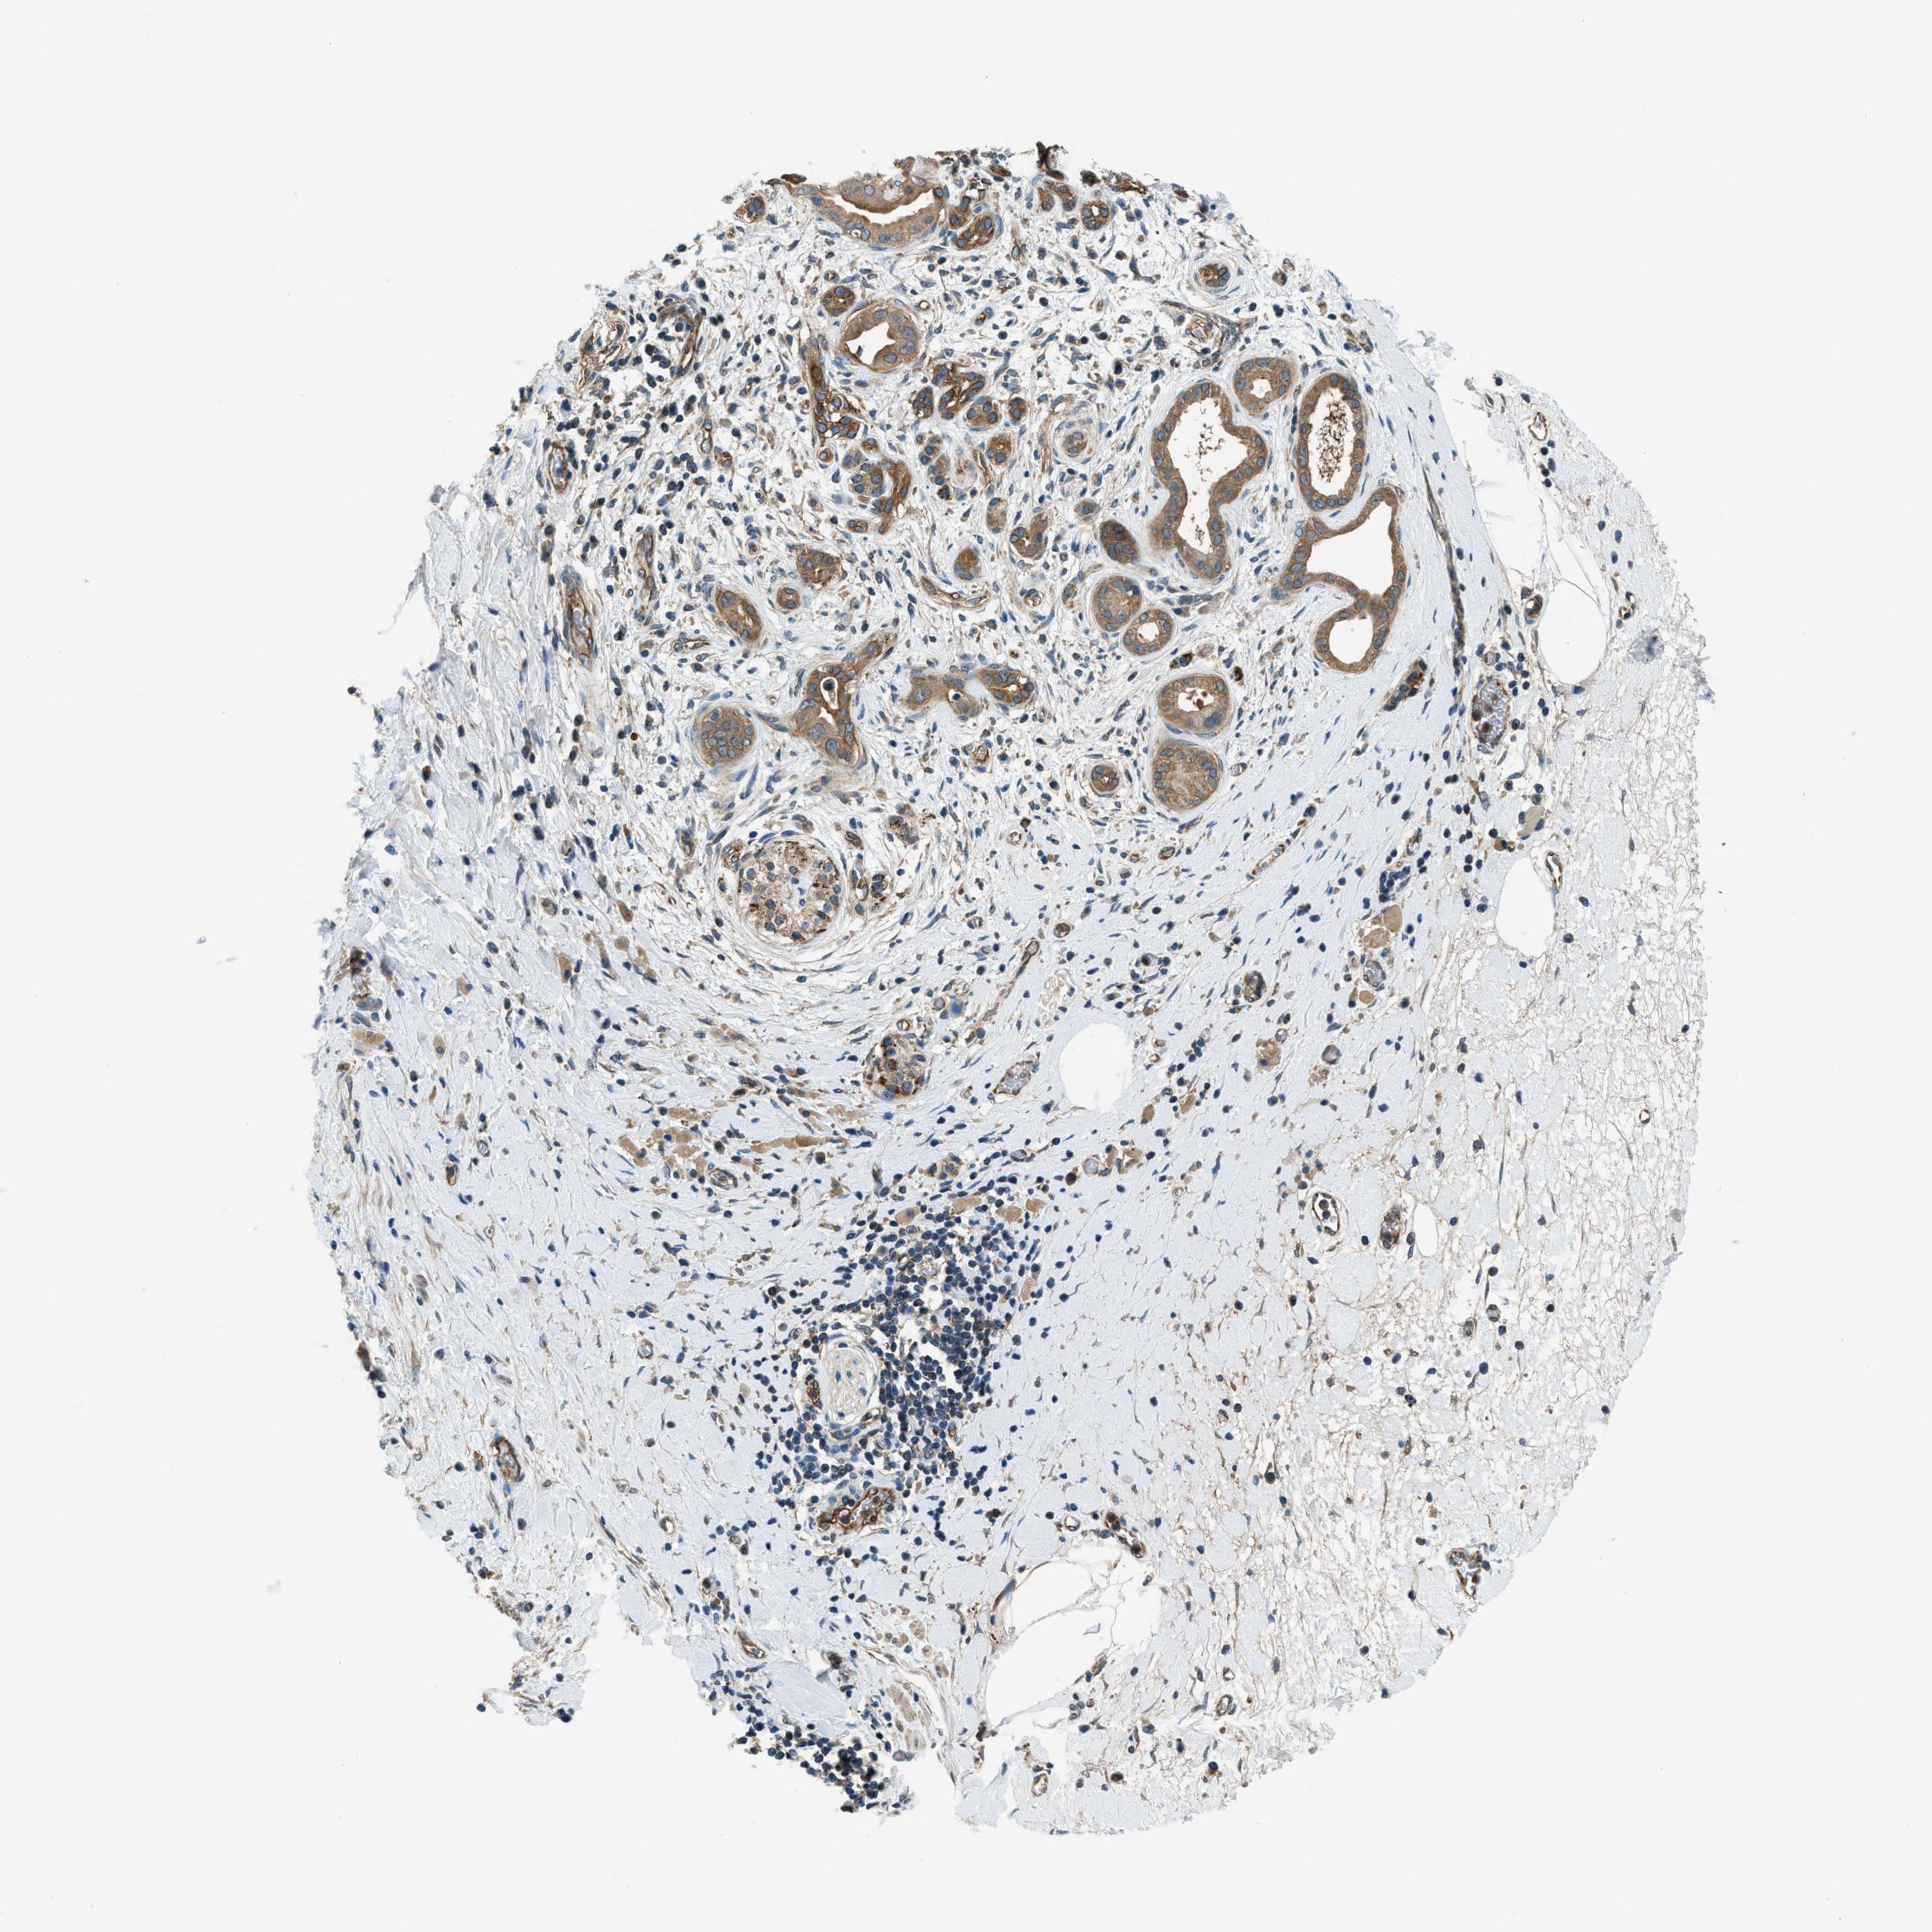

PANCREATIC CANCER - Protein expressioni

A mouse-over function shows sample information and annotation data. Click on an image to view it in a full screen mode. Samples can be filtered based on level of antibody staining by selecting one or several of the following categories: high, medium, low and not detected. The assay and annotation is described here.

Note that samples used for immunohistochemistry by the Human Protein Atlas do not correspond to samples in the TCGA dataset.

Antibody stainingi

Antibody staining in the annotated cell types in the current human tissue is reported as not detected, low, medium, or high, based on conventional immunohistochemistry profiling in selected tissues. This score is based on the combination of the staining intensity and fraction of stained cells.

Each image is clickable and will lead to virtual microscopy that enables deeper exploration of all samples and also displays staining intensity scores, fraction scores and subcellular localization as well as patient and tissue information for each sample.

Antibody HPA006119

Antibody HPA016599

Staining

High

Medium

Low

Not detected

Intensity

Strong

Moderate

Weak

Negative

Quantity

>75%

75%-25%

<25%

None

Location

Nuclear

Cytoplasmic/membranous

Cytoplasmic/membranous,nuclear

Adenocarcinoma, NOS

Adenocarcinoma, metastatic, NOS